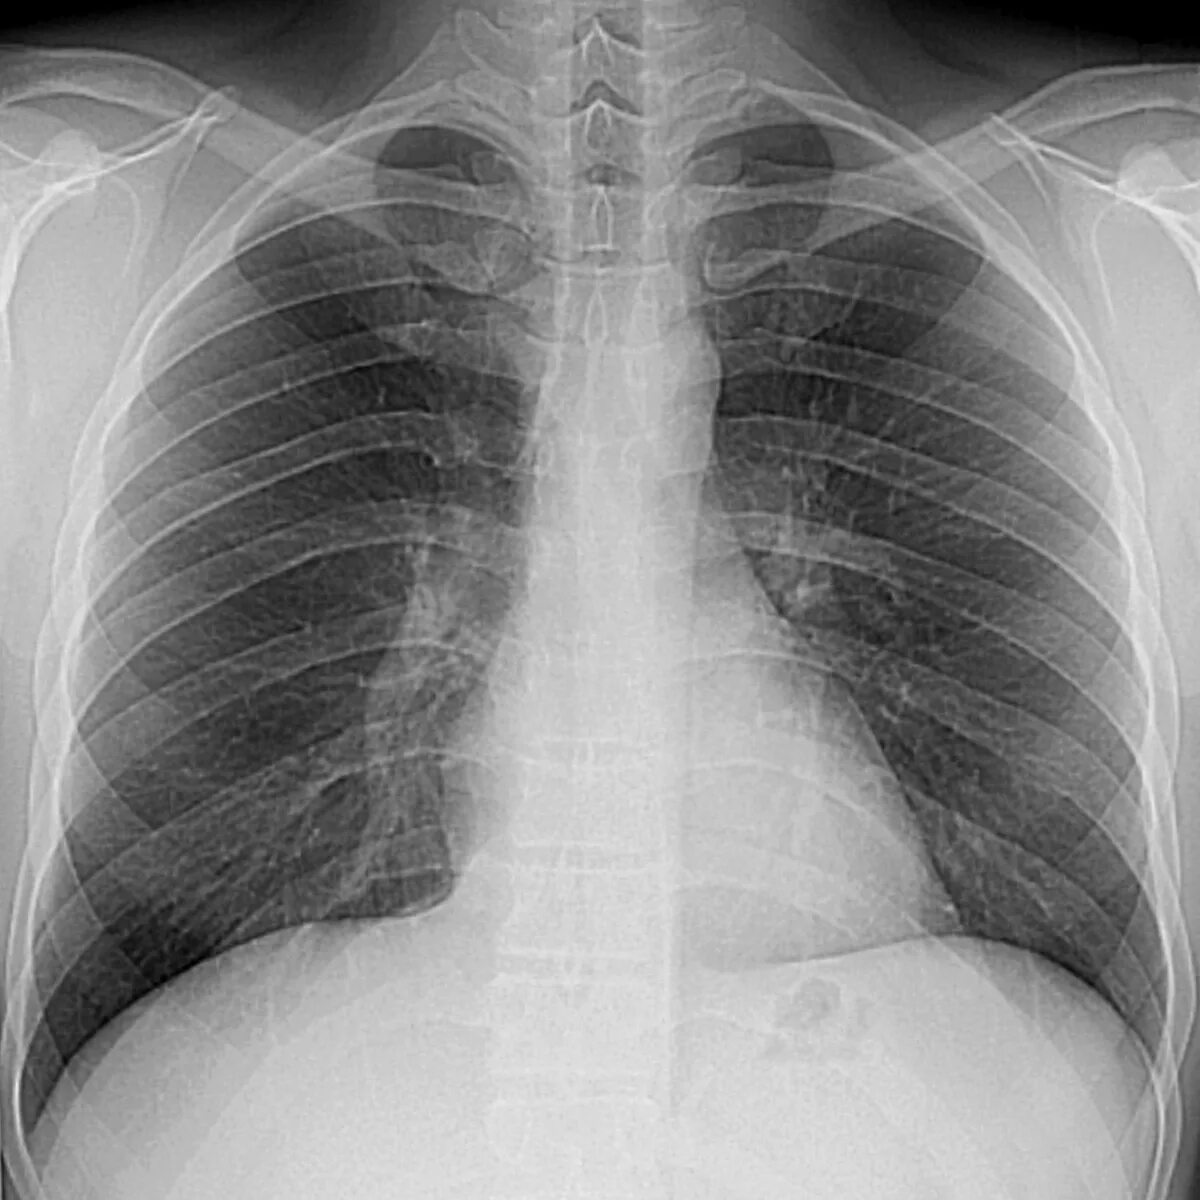

Ээд легких